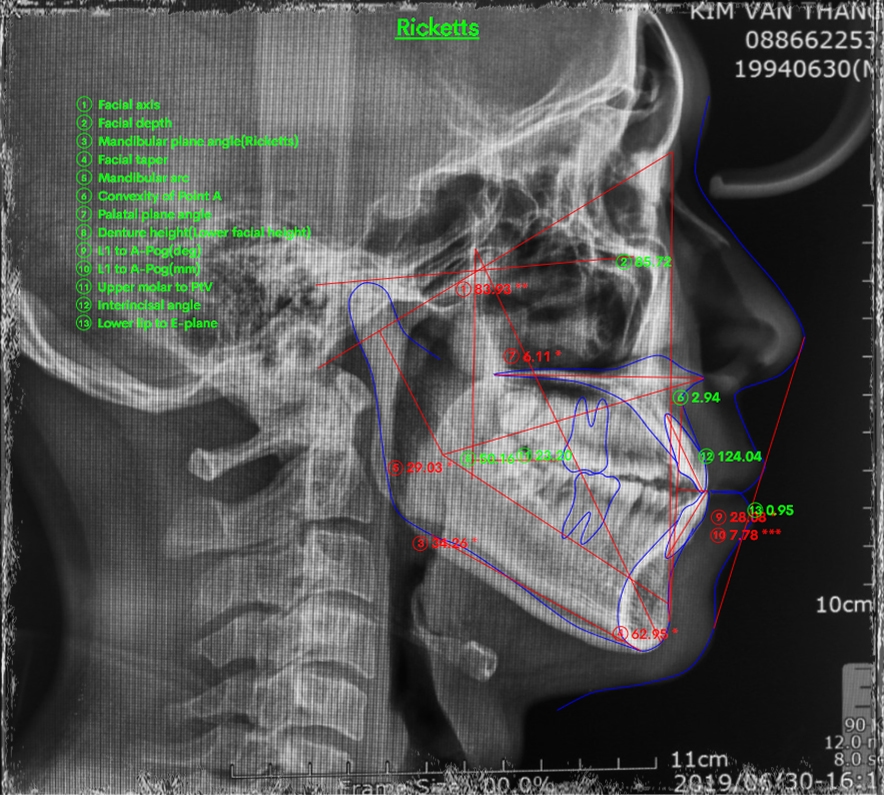

BN nam sinh năm 1994 khớp cắn hạng III, răng chen chúc. BN có sự phát triển không đồng đều của xương hàm dưới hai bên dẫn đến biến chứng lệch mặt. Kết hợp cả yếu tố sai khớp cắn do răng làm hàm dưới vừa lệch do xương lại vừa lệch do thích nghi chức năng. BN đã được nhổ 3R4 để giải quyết vấn đề chen chúc răng và kéo lùi nhóm răng cửa dưới.

Tình hình khi gặp gỡ: còn nhiều khoảng nhổ răng, khớp cắn ngược răng cửa, cắn chéo nhóm răng hàm cung 1. Đường giữa hàm dưới lệch nguyên 1 răng cửa. Mặt thẳng lệch rất rõ, cằm đưa hẳn sang bên phải.

Xử lí: Đóng khoảng hàm dưới đến mức vừa phải để giải quyết cắn ngược răng cửa. Bẻ MEAW trên TMA 17×25 định vị lại vị trí xương hàm dưới. Sau đó chuyển lại kĩ thuật dây thẳng để kết thúc sau gần 2 năm.

Kết quả: đường giữa gần như thẳng, xương hàm dưới định vị về vị trí bình thường. Khuôn mặt cải thiện khá so với trước điều trị nhưng không thể hoàn hảo do căn nguyên sai lệch kết hợp đến từ sai lệch xương ![]()